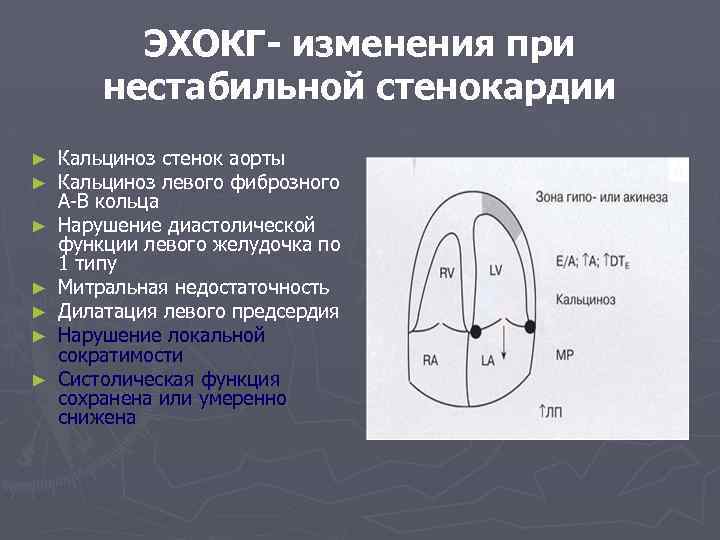

ЭХОКГ- изменения при нестабильной стенокардии ► ► ► ► Кальциноз стенок аорты Кальциноз левого фиброзного А-В кольца Нарушение диастолической функции левого желудочка по 1 типу Митральная недостаточность Дилатация левого предсердия Нарушение локальной сократимости Систолическая функция сохранена или умеренно снижена